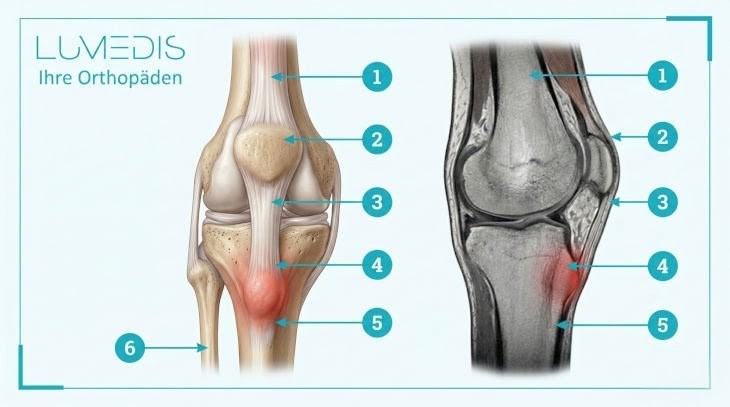

Abbildung eines Morbus Osgood-Schlatter

Abbildung der Sehnen und Bänder des Kniegelenks